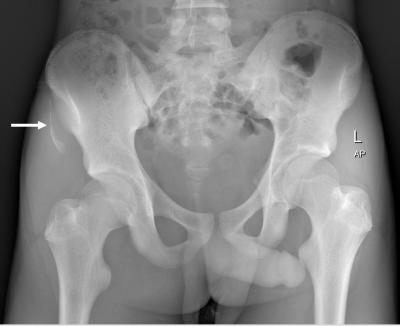

Avulsion Fracture of Pelvic Apophyses

anterior superior iliac spine

avulsion fracture